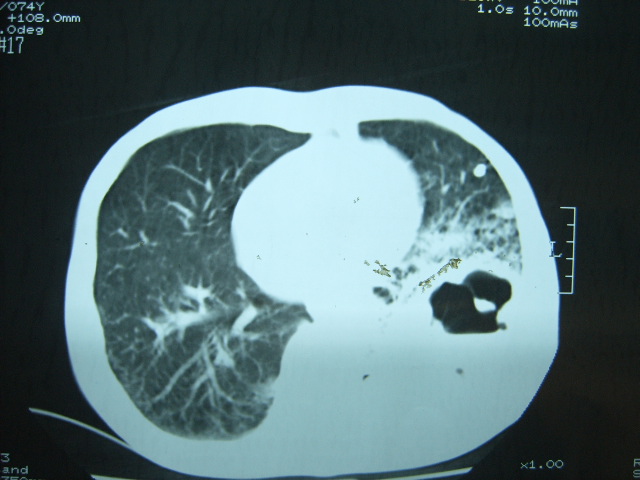

男74岁,咳嗽,寒战,低烧。有糖尿病史。

两肺结核,空洞形成,左下肺肺段隔离症待排

1、左下肺肺脓肿,合并霉菌球形成?.2、双肺陈旧性病灶.3、右上肺病灶警惕瘢痕癌,建议定期复查.

两肺结核,左下肺空洞性病变,结核性?炎性?癌性?抗炎治疗后复查。

两肺结核,左下肺大片实变,内见空洞性病变,壁不规则,结合糖尿病史,考虑:结核性?霉菌性?建议结合实验室检查或治疗后复查。